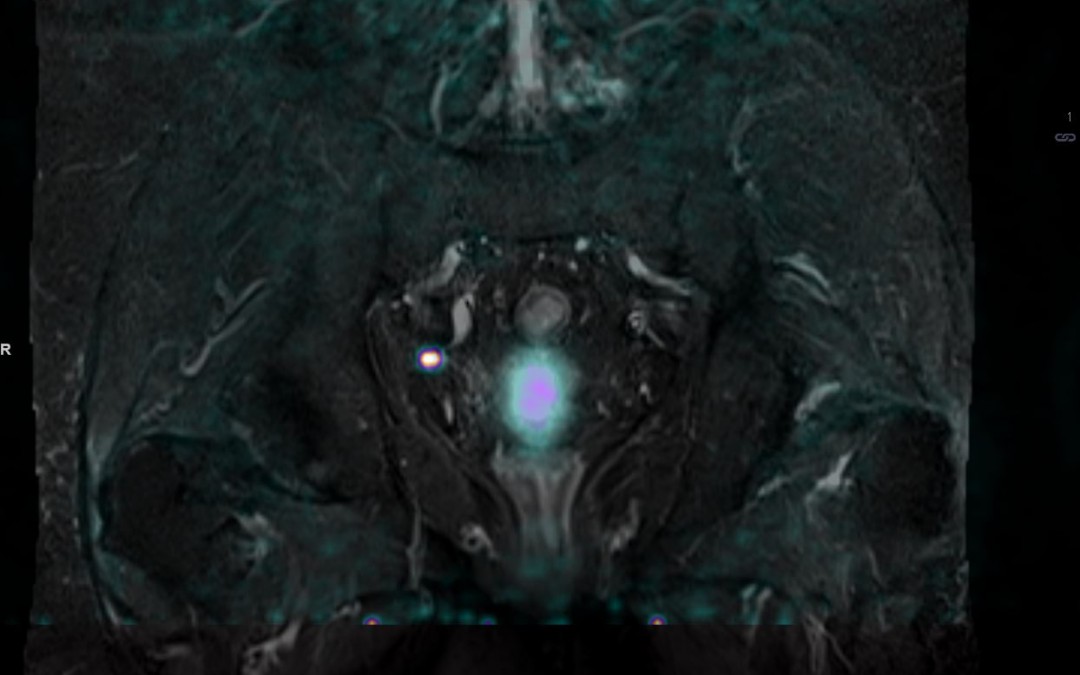

[99mTc]-PSMA: xSPECT/CT Fig 1. [99mTc]-PSMA uptake in a presacral node pre and post therapy Fig 2. [99mTc]-PSMA prostate uptake pre and post therapy Mr WB is a 61 yr old man with a diagnosis of Gleason 9 prostate cancer after a biopsy in May 2017. A subsequent MRI...